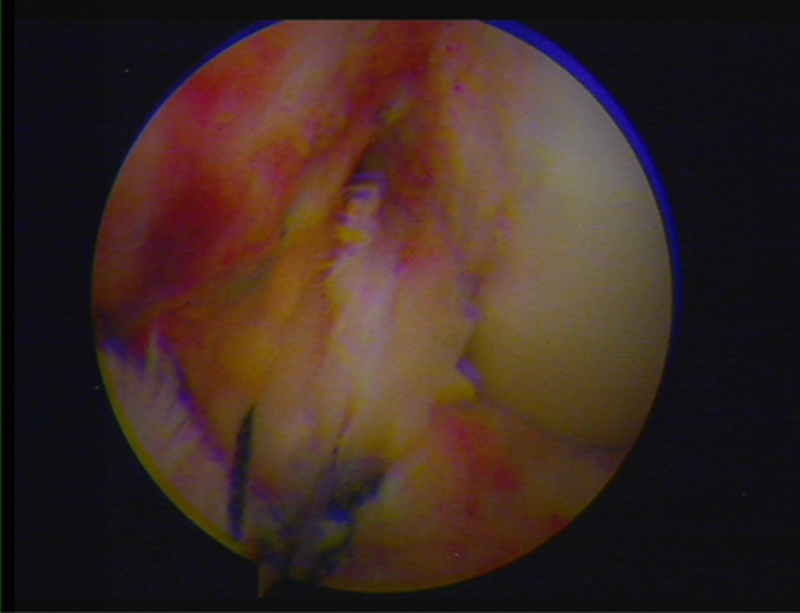

镜下显示ACL残束